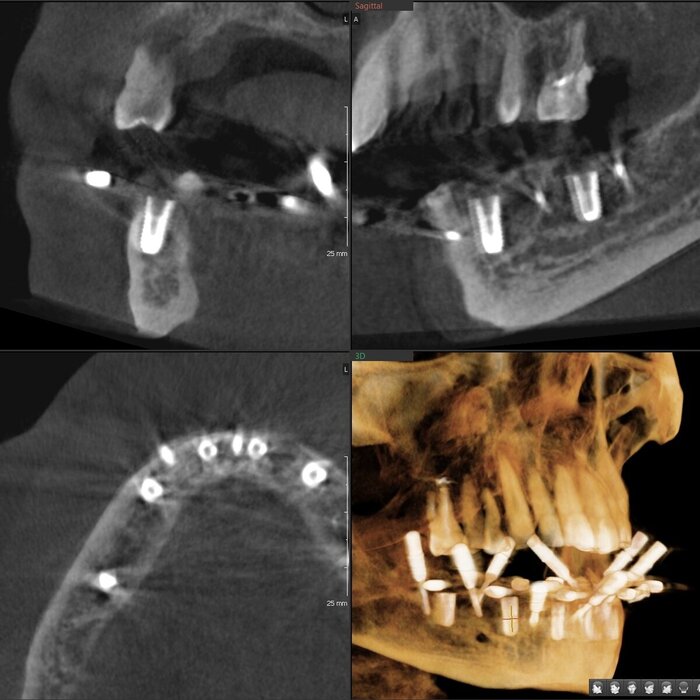

Пока верх не закончен, можно переходить к низу. Тут всё проще (как это часто и бывает). Выбор сделан в пользу тотальной работы на 6 имплантатах (сверху, по итогу, будет то же самое).

Для операции нам требовался снимок КЛКТ и цифровой слепок челюстей. Всё это пациент сделал в своём городе.

Часа через 2.5-3 имплантаты были установлены.

Результат такой - торки получены эталонные везде, кроме двух крайних имплантатов слева (3.4 и 3.6). Но не страшно, сверху зубов-антогонистов нет, нагрузки на протез не будет серьёзной. Да и "всё на 6" прощает подобное.

Протез будет с розовой десной и-за дефицита тканей (FP3).